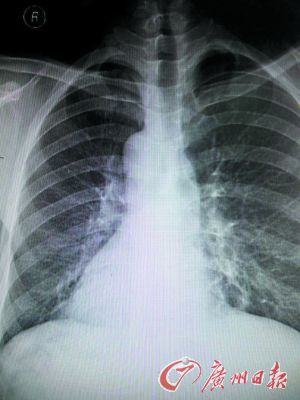

X光片上患者的心脏阴影在右边。

医生赶快拿起听诊器听诊心音区,发现患者右侧心音较左侧明显,跟常人相反。经胸片、心电图及B超等检查后,确诊患者为急性化脓性阑尾炎内脏反位,也就是“镜面人”得了阑尾炎。